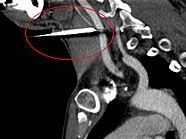

Das Projektil habe die Hauptschlagader nur um Millimeter verfehlt, sagte ein Beamter der Polizeiinspektion Lamprechtshausen der APA auf Anfrage. Der Verletzte wurde in das Landeskrankenhaus Salzburg geflogen.

Der Unfall ereignete sich um 8.45 Uhr bei Dachreparaturarbeiten. Der Zimmerer wollte Windleisten am Giebel befestigen. Dabei rutschte der 33-Jährige auf einem feuchten Brett aus und drückte im Sturz ungewollt auf den Auslöseknopf. Der so abgefeuerte Nagel traf den Mann an der linken Halsseite. Der Arbeiter wurde versorgt und dann mit dem Hubschrauber in Krankenhaus geflogen.